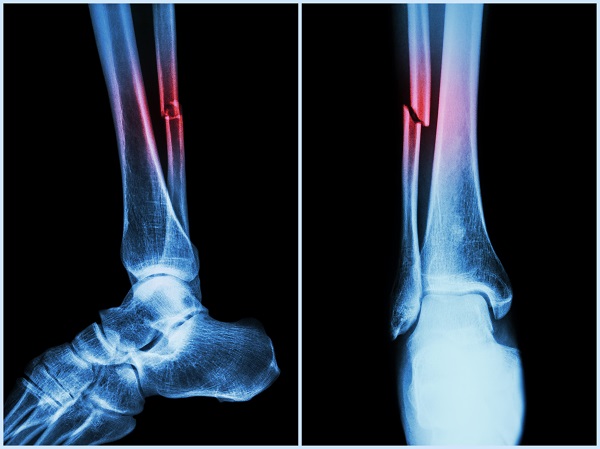

The most common injuries related to intimate partner violence were; 18% fractures of the foot or ankle 14% hand or wrist fractures and other fractures in more than one location 18%.